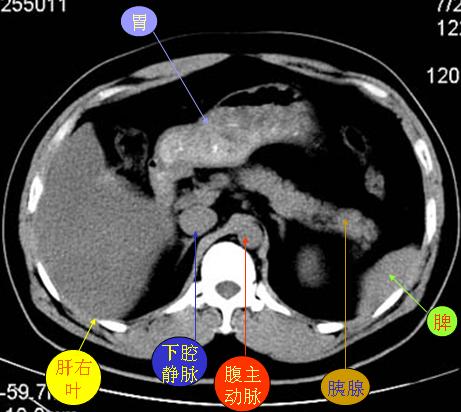

腹部ct解剖与基本病变